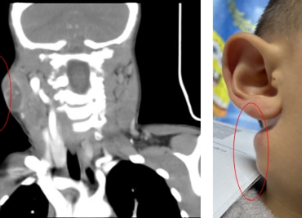

颈部CT示意图。

入院后,学生儿童结核科副主任周海依为孩子进行了仔细的检查,发现孩子颈部有多发淋巴结肿大,右下颌处有一直径约3CM的包块,表面红肿破溃,按压有波动感;左侧有三个包块,最大的直径为2.5CM左右。经过进一步完善检查,认为结核病诊断依据不足,联合耳鼻咽喉头颈外科副主任、主任医师周定刚会诊,明确有手术指征,转耳鼻咽喉头颈外科,完善术前准备后行双侧颌下淋巴结清扫术+皮瓣修整术。

术前术后对比图。